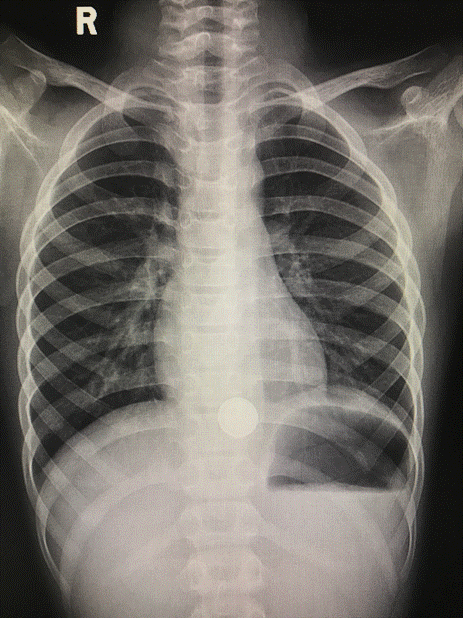

5月24日晚上儿童急诊接诊了一位胸痛的男孩,询问病史,一小时前在学校捡到一个异物,放到嘴巴里玩,一不小心就误吞了,具体什么性质、什么形状描述不清。在之后回家就出现胸痛,我立即予拍胸片检查,结果显示金属类纽扣样物。

这时我马上考虑到纽扣电池可能,紧急联系儿科胃镜专科吴主任医师。吴主任到场后评估患儿情况,予急诊胃镜取出。通过仔细辨认,这是一枚已经发黑的纽扣电池,在这个过程中发现食管壁接触面见腐蚀糜烂,再晚几个小时,后果不堪设想。